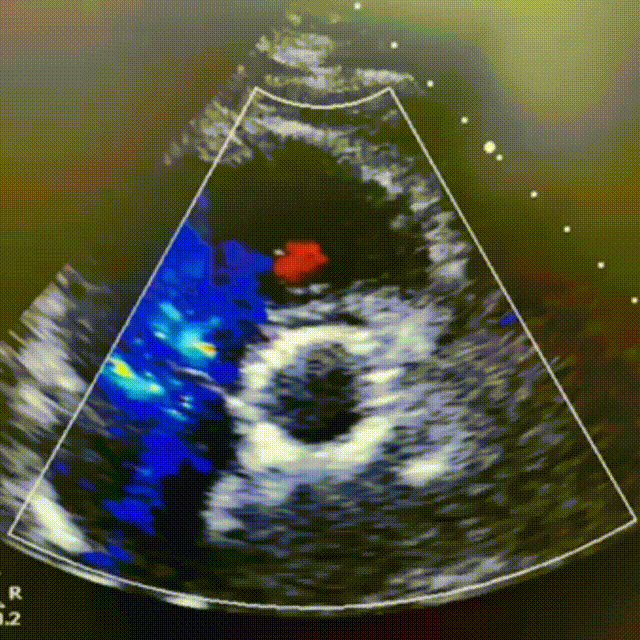

超声影像

TTE下主动脉瓣短轴和五腔心角度下,血流动力学结果优异,反流即刻消失。